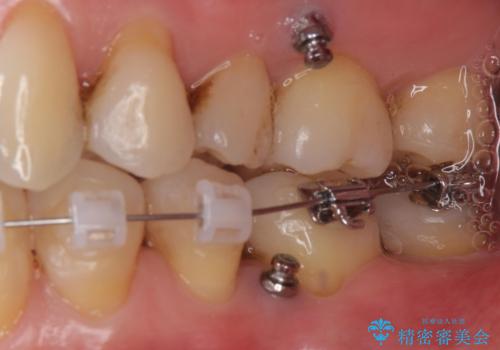

左下の奥歯が内側に倒れこみ、左上の奥歯は向きが悪くすれ違っていました。

ワイヤー矯正とマウスピース矯正を併用し、左上の位置が悪い歯は抜歯し、左上の親知らずを手前に移動させました。

左上下のかみ合わせが悪く、歯石も多かったため、歯周病の治療も併せて行いました。

難易度の高い部分はワイヤー部分矯正を行うなどして対応し、見える部分はマウスピース矯正を併用する工夫を行いました。